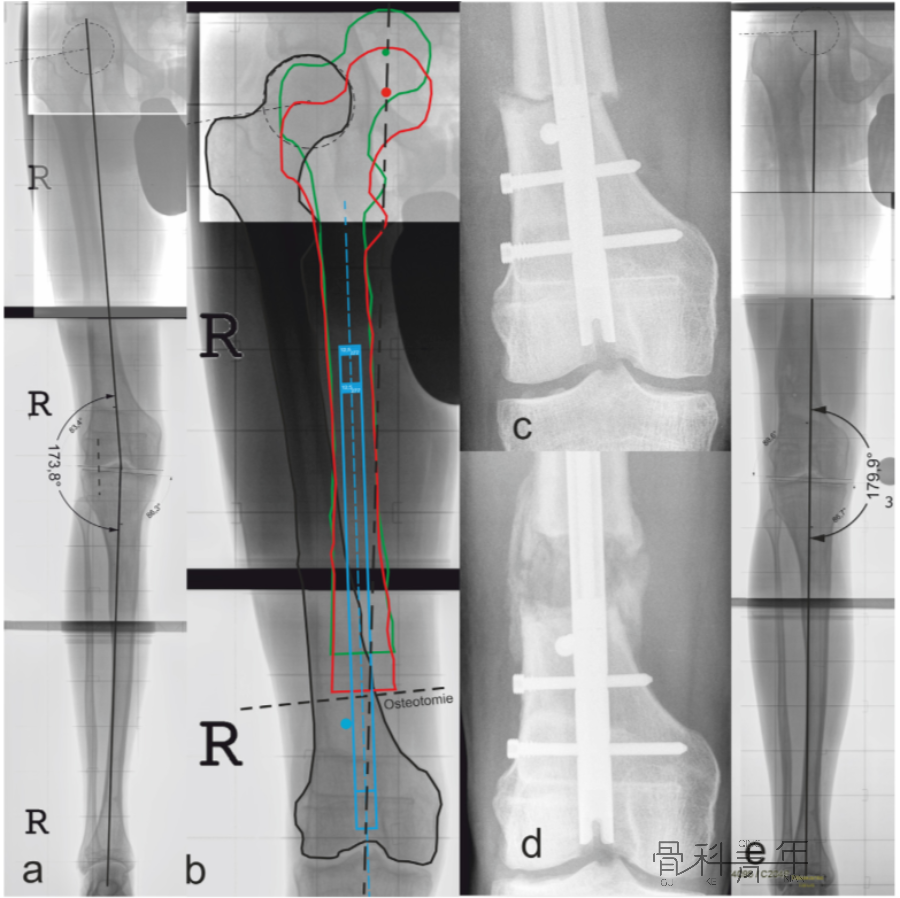

为了矫正股骨力线,在干骺端横行截骨(a横行虚线)后,截骨远端移位,此时髓内钉置入后应为偏心方可维持矫形,为了获得髓内钉位置,需要置入阻挡钉(b)。

图a所示该患肢与健侧相比,存在6.2°外翻和28mm短缩。图b红色轮廓为纠正力线后截骨近端的形态,绿色为同时纠正外翻和短缩后股骨近端的位置,依照绿色轮廓置入髓内钉,此时髓内钉进入截骨远端为偏心,为了维持髓内钉位置,阻挡钉置入位置明确。图d可见髓内钉及阻挡钉置入后情况。

依上述理论及病例解析,不难发现,无论对于股骨或胫骨,无论畸形方向,均可以通过阻挡钉来位置髓内钉位置。各部位及各畸形状况下阻挡钉置入位置如下图: